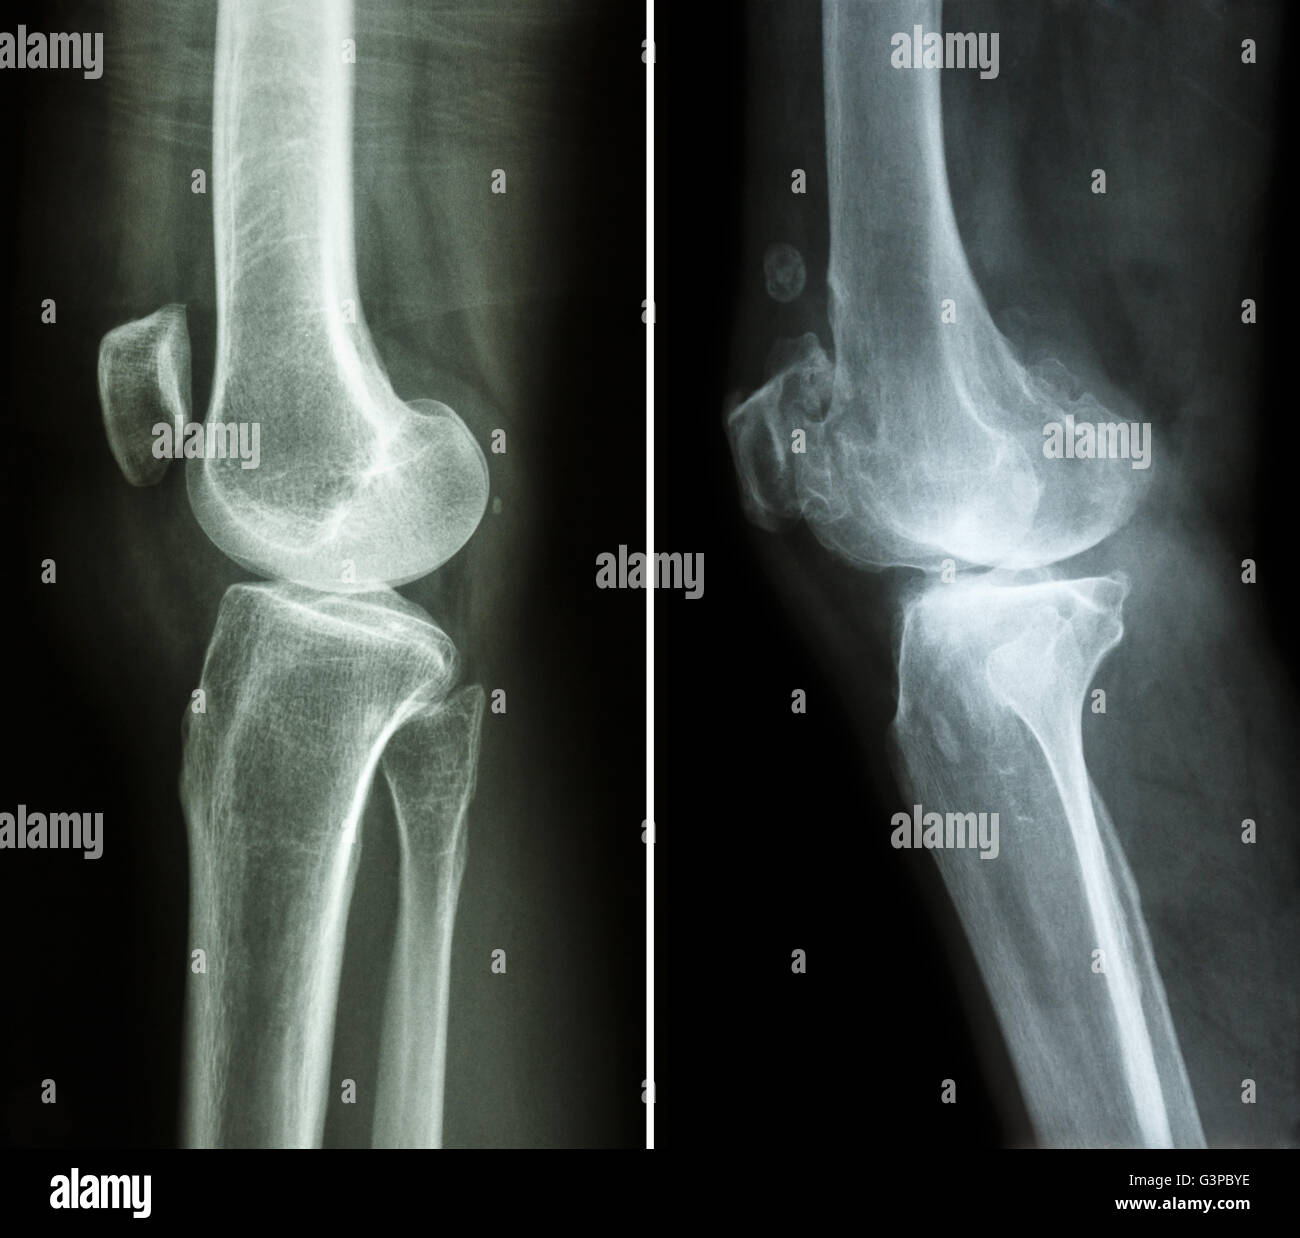

Film X-ray montrent l'articulation du genou normal(AP/latéral) Banque D'Imageshttps://www.alamyimages.fr/image-license-details/?v=1https://www.alamyimages.fr/photo-image-film-x-ray-montrent-l-articulation-du-genou-normal-ap-lateral-77387023.html

Film X-ray montrent l'articulation du genou normal(AP/latéral) Banque D'Imageshttps://www.alamyimages.fr/image-license-details/?v=1https://www.alamyimages.fr/photo-image-film-x-ray-montrent-l-articulation-du-genou-normal-ap-lateral-77387023.htmlRFEDW7X7–Film X-ray montrent l'articulation du genou normal(AP/latéral)